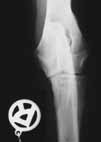

| Zugelassene

Röntgenstelle für HD

(Hüftgelenksdysplasie), ED

(Ellenbogengelenksdysplaie) und OCD

(Osteochondrosis dissecans). |